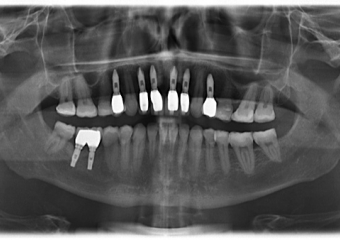

Raio X final